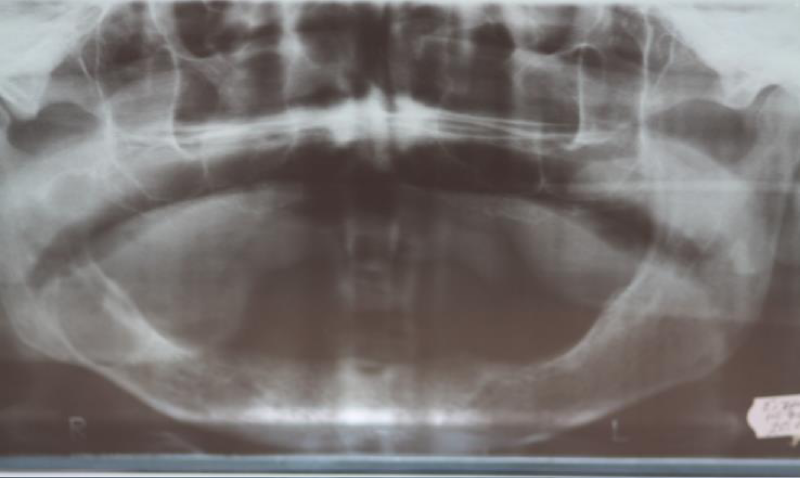

A.E 72-year-old man, was treated in the department of head and neck surgery of RECUH (Riga East Clinical University Hospital) LOC (Latvian Oncological Center) with diagnosis: Cysta mandibula dxt. Complication: Phlegmona colli bilateralis (Necrotizing fasciitis). The patient came to the clinic with complaints about a lesion in the right side of the mandibula, and secretions from the lesion. According to anamnesis morbi, the patient believes that everything started in January 2009, when he felt an increasing mass and secretions in his mouth, and that his mandibular complete denture didn’t fit him as well as before. In July 2010, the patient went to the Institute of Stomatology department of surgery, where radiographically he was diagnosed with a cystic lesion that was punctured. Cytological examination diagnosed a cyst with a secondary inflammation. Patient was informed about the need for surgery, but he declined for family reasons. In 22.10 2010 the patient had an exacerbation of the inflammation, that manifested as facial asymmetry and an increase of secretions in the mouth, beforehand the patient had visited a private dental practice where he received an incision that released a purulent discharge. The patient was given a mouth wash, and post operation antibacterial therapy- Amoxiclav 625mg 3 times a day, as well as analgesic therapy- Ibuprophen 400mg 3 times a day. In a week, there was a noticeable decrease in the volume of the formation, but the patient still was bothered with the constant discharge from the wound, that’s why he went to the department of maxillofacial surgery at the Center of Oncology of Latvia. There was a noticeable asymmetry of the face due to the swelling of the left cheek. A noticeable formation was seen intraorally on the edentulous arch, it was located in the molar, retromolar and ascending ramus region. When palpating the wound, a cloudy discharge was noticed. Radiographically in the panoramic image a well-defined cystic lesion was noticed in the right side of the mandibular corpus and lower third of the ascending ramus (Figure 1).